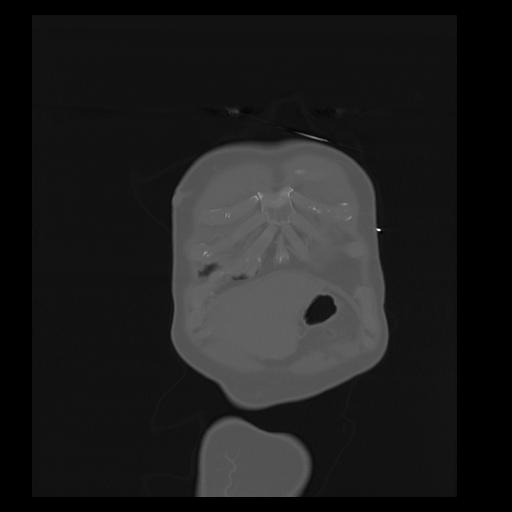

32 PULMON,CE,Coronal,3.000,PULMON,Coronal,